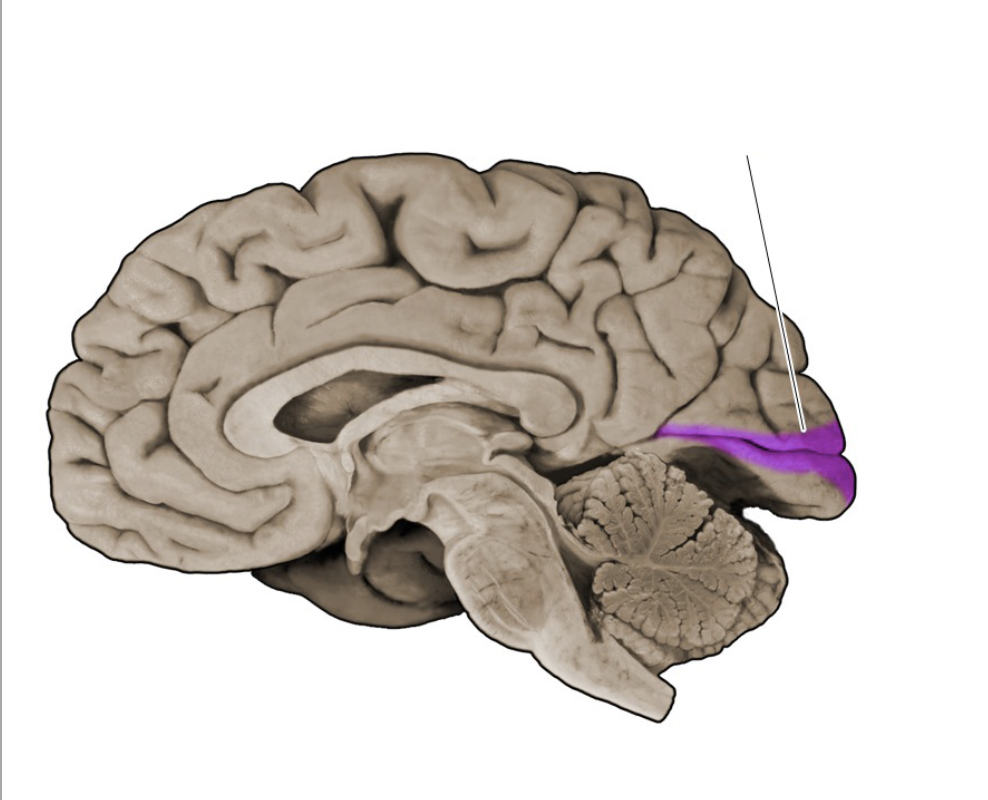

Calcarine sulcus

A prominent sulcus in the medial occipital lobe formed by the cuneus and lingual gyral structures; this sulcus extends roughly horizontally from the parieto-occipital sulcus to its termination in the occipital pole. The calcarine sulcus contains the primary visual cortex (also called the "striate cortex").

Parieto-occipital sulcus

Prominent vertically oriented sulcus on the medial aspect of the hemisphere that divides the parietal and occipital lobes; intersects the anterior terminus of the calcarine sulcus at nearly a right angle.

Primary visual cortex

Cortical area (Brodmann's area 17; also referred to as the "striate cortex") in the banks of the calcarine sulcus that first receives visual signals from the relevant thalamic nucleus (lateral geniculate nucleus).